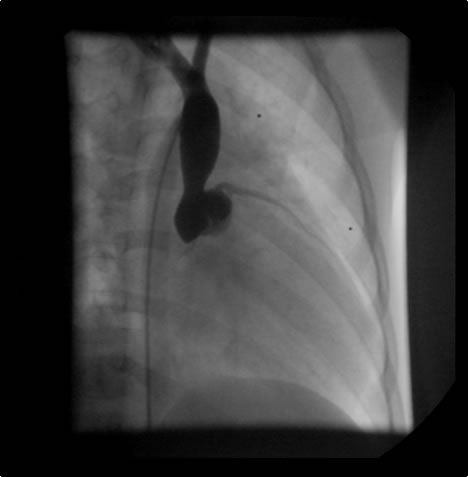

Figure 3: AP completion venogram on day 2 after mechanical thrombolysis and TPA infusion overnight and post-deployment of overlapping "kissing" Wallstents. Notice improved drainage into the right atrium on post-deployment venogram.

Re-imaging the following day or twelve hours later is necessary with the objective being bilateral upper extremity venograms showing a significant improvement in venous thrombosis and clot burden. Placement of two self-expanding Wallstents (Boston Scientific Inc., Natick, MA) stents centrally utilizing a "kissing stent" deployment technique [16] is warranted to avoid compression of the contralateral vessel and prevent compression of the flow channel: a 20 mm x 40 mm stent in the superior vena cava and right subclavian vein and a 14 mm x 40 mm stent in the innominate vein and superior vena cava (Figure 3). Stent sizes are selected according to patients' needs.